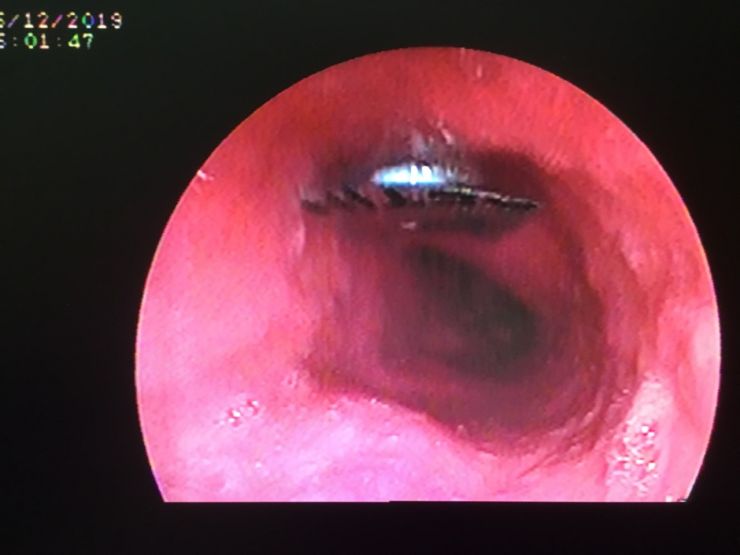

Chiều ngày hôm trước, bệnh nhân vào Khoa Cấp cứu trong tình trạng đau tức ngực sau xương ức do nuốt phải vỏ thuốc còn nguyên vỏ. Sau đó, bệnh nhân được chuyển vào phòng Nội soi để tiến hành nội soi, chẩn đoán cho thấy dị vật viên thuốc còn nguyên vỏ kích thước 9 x 9mm, hình vuông cạnh sắc bén như dao ở thực quản đoạn giữa, có nguy cơ gây thủng thực quản vào trung thất có thể dẫn đến tử vong.

Để tránh nguy cơ viên thuốc sặc vào phổi, Đơn vị Nội soi mời bác sĩ Khoa Gây mê hồi sức tiến hành tiền mê để nội soi gắp dị vật an toàn cho bệnh nhân. Do dị vật sắc bén nên ê kíp bác sĩ phải dùng chụp dị vật bằng silicon để bao dị vật tránh chảy máu và thủng thực quản khi kéo dị vật ra ngoài.